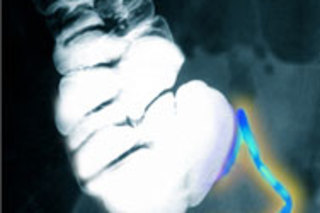

阑尾(在此X光片中显示为蓝色)是否能保持肠道健康?图片:Scott Camazine/Photo Researchers